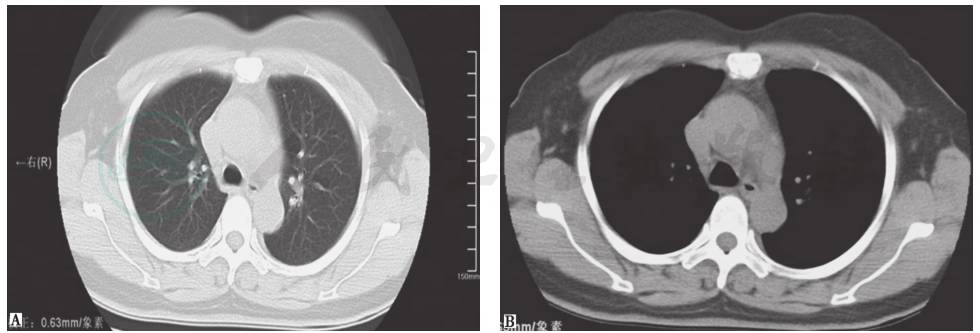

结合患者病史、临床表现及各项检查结果,本病例结核性胸膜炎诊断明确,并且考虑合并结节病。治疗方案采取异烟肼(isoniazid,INH)0.3g(每天1次)、利福平(rifampicin,RFP)0.45g(每天1次)、乙胺丁醇(ethambutol,EMB)0.75g(每天1次)、吡嗪酰胺(pyrazinamide,PZA)0.5g(每天3次)抗结核,同时给予激素治疗。患者症状缓解,出院后亦无不适主诉,坚持2HRZE/10HRE方案抗结核治疗,胸腔积液逐渐吸收。7周后复查胸部CT,发现纵隔淋巴结明显缩小(图13)。正规治疗1年后,患者停药,胸部CT提示纵隔肺门未见明显肿大淋巴结(图14)。

图13 治疗7周后复查胸部CT表现

胸部CT显示纵隔淋巴结明显缩小,胸腔积液明显吸收

图14 治疗1年后复查胸部CT表现